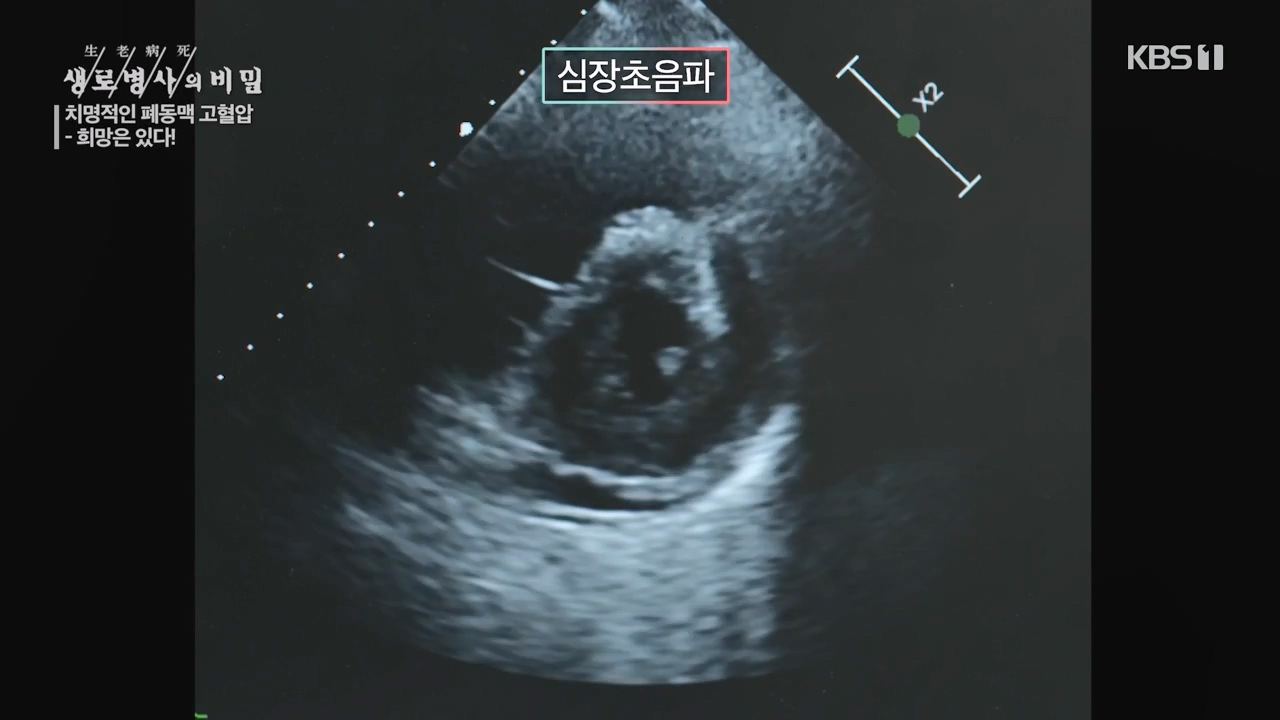

생로병사의 비밀, 이유없이 숨이 찬 증상이 오래간다면...세상에서 가장 슬픈 병 '폐동맥 고혈압' 생존율 높인 최신 약제 방송을 보고나서.

[한국강사신문 이미숙 기자] 폐동맥이 두꺼워져 심장과 폐순환의 압력이 높아지는 폐동맥 고혈압! 폐동맥 고혈압은 과거, 쓸 수 있는 약이 없어 진단...